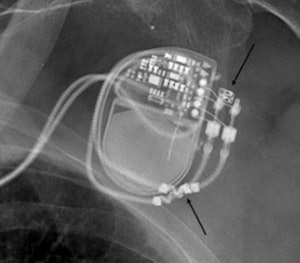

A pre-MRI x-ray allows visual confirmation of electrode placement and integrity, implantable pulse generator position, and MR-conditional radiopaque markers. Top arrow indicates radiopaque emblem of an MR-conditional pacemaker. Bottom arrow indicates appropriate electrodes or "leads" with MR-conditional wavy radiopaque markers. Image courtesy of Dr. Josef Vymazal.

First, an initial standard x-ray will allow radiologists to check that the pacemaker is MR-conditional, not conventional, and that the correct electrodes (or "leads") are present. Energy from the magnetic field transforms into heat and may be conducted by the electrodes into the heart. Such a temperature increase in a standard pacemaker may damage the myocardium and cause necrosis, one reason for disqualifying MRI in these cases. In an MR-conditional pacemaker, however, this temperature increase should be minimal due to differences in the electrodes' composition and will not cause damage.

"So far it is unclear whether or not the electrodes can be replaced at a later stage by different noncompatible ones, by error, for example. I am only happy when I've seen with my own eyes through a simple x-ray that all is as it should be. This is my first precaution," he explained.